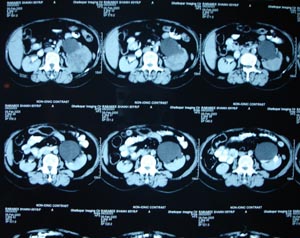

Renal cell carcinoma

Left renal cell carcinoma. Solitary mass arising within the renal cell parenchyma, not cystic in nature is most likely to be malignant in nature.In adults mostly it is renal cell carcinoma (In children mostly it is wilms’ tumour)